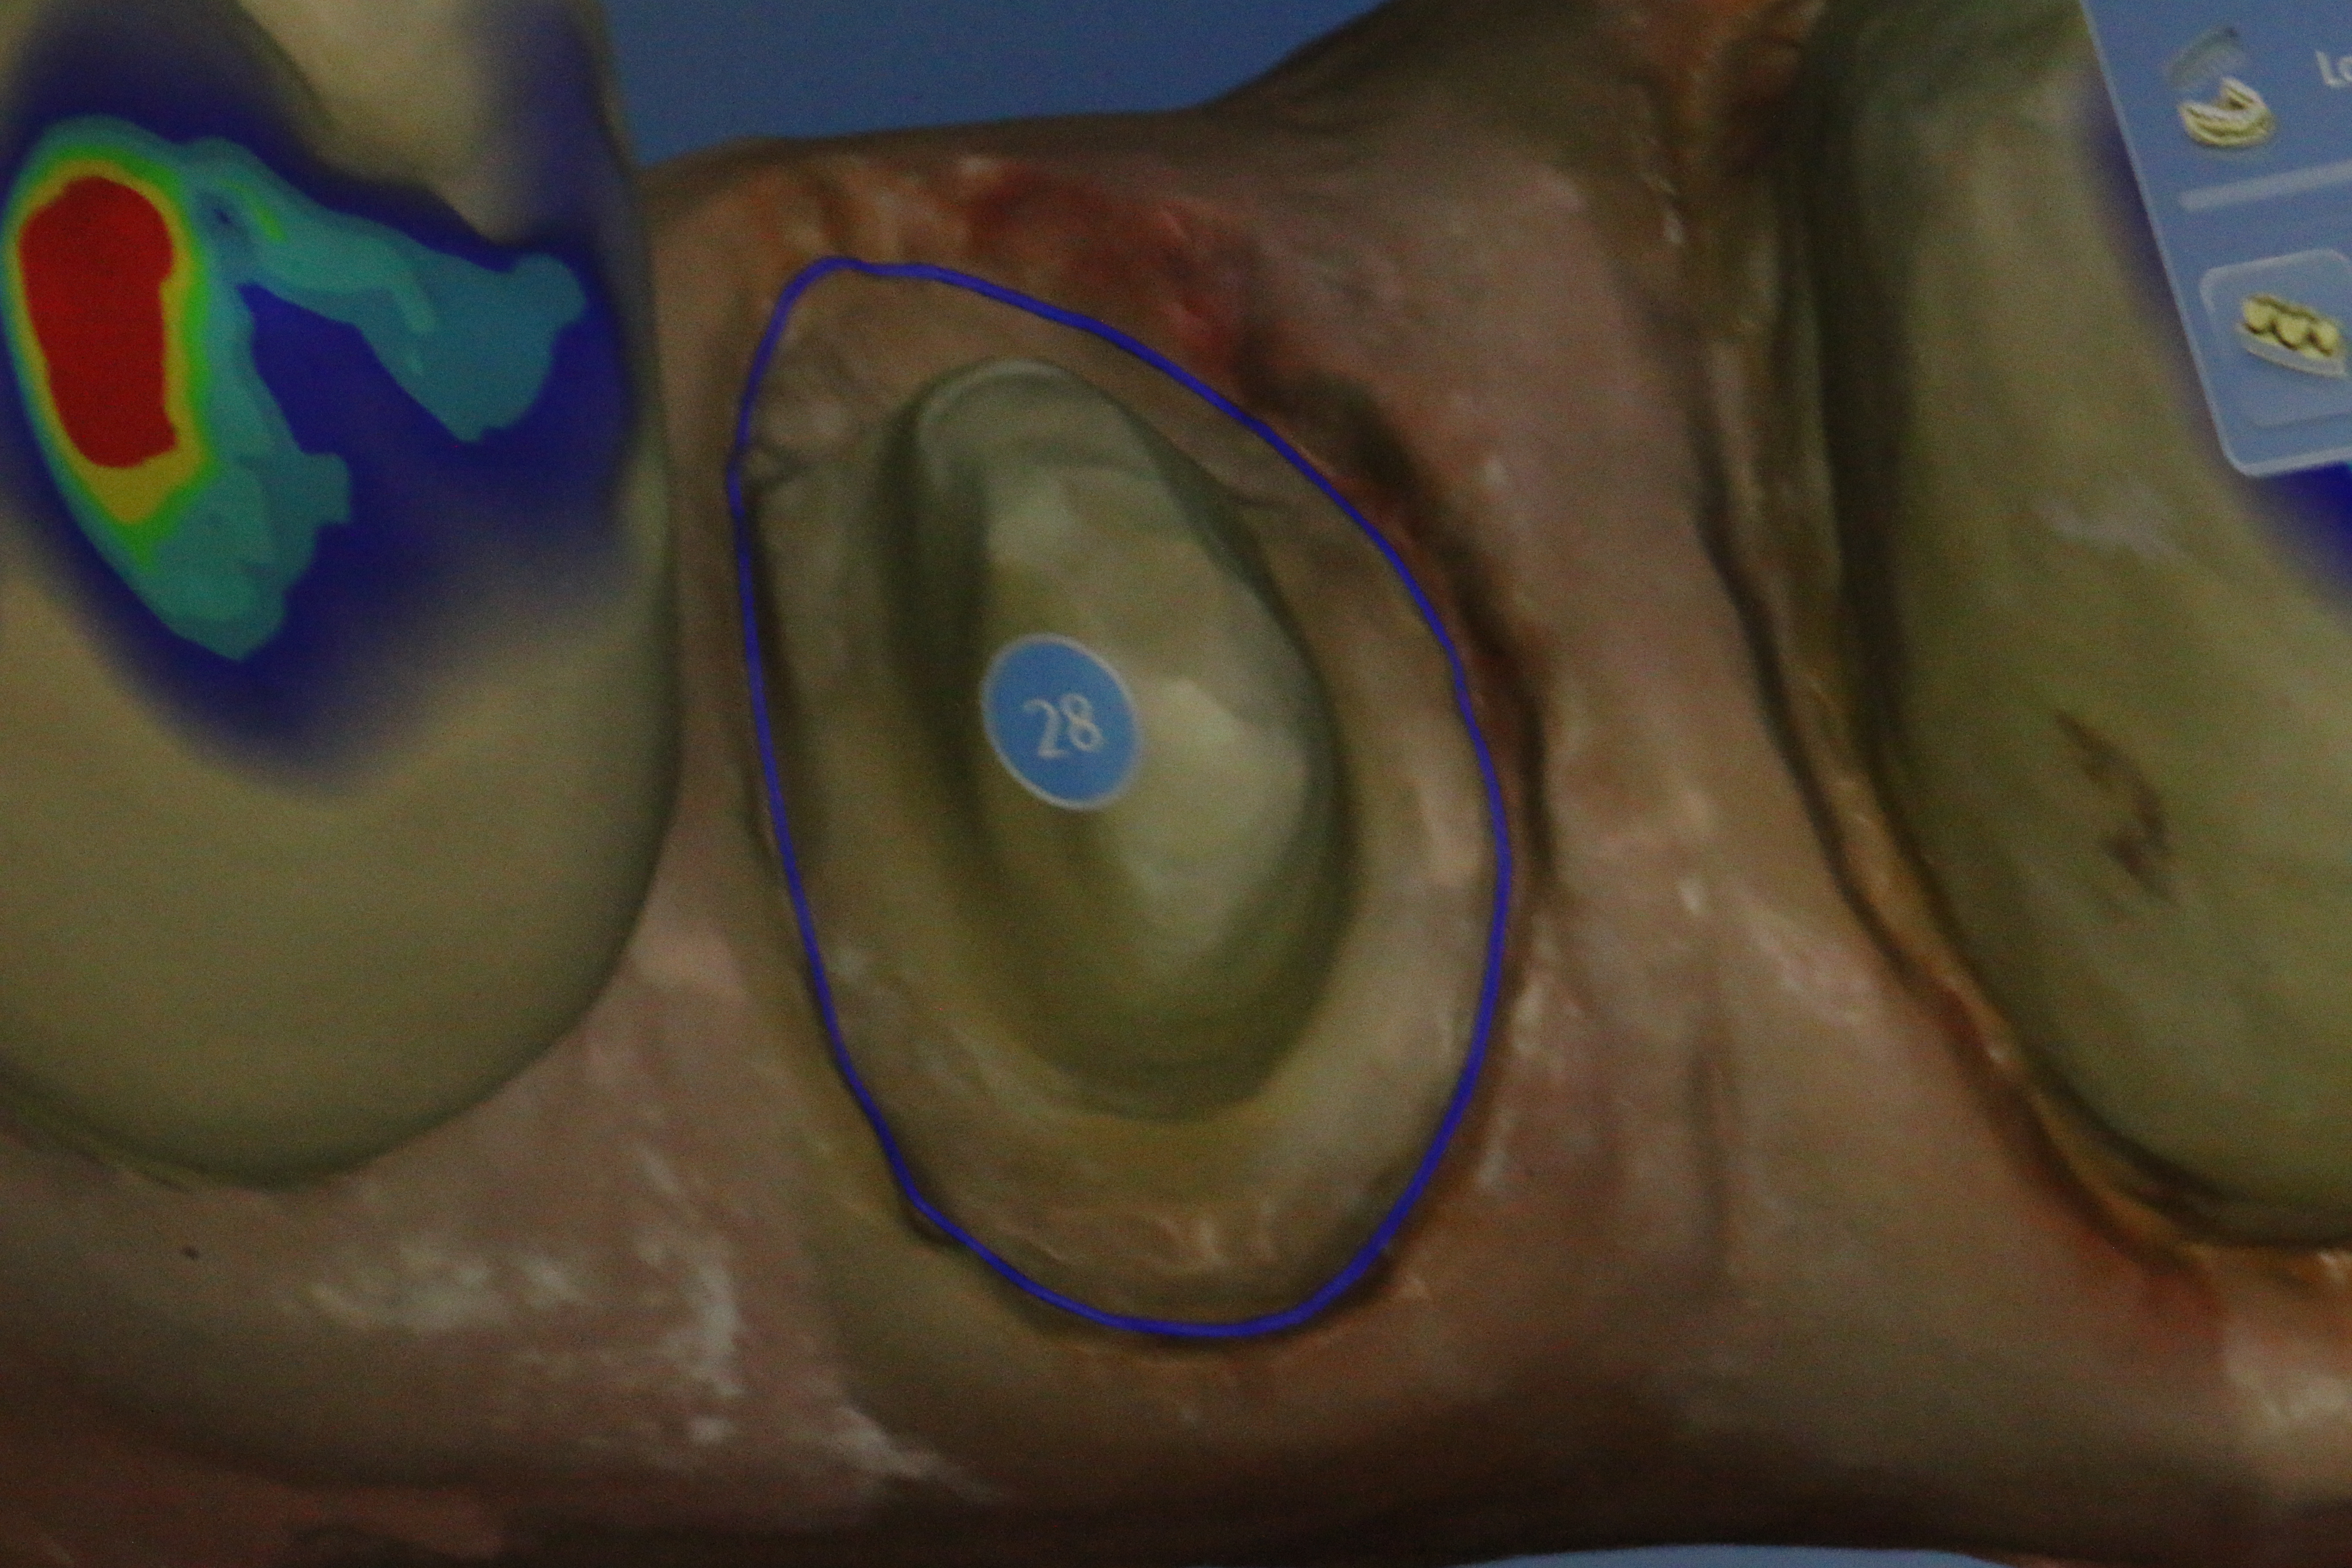

CAD/CAM dentistry is very precise. For accuracy, the preoperative, shade, bite, and upper/lower tooth scans are best taken before anesthesia and dental procedures that induce muscle fatigue (Figure 3). After infiltration anesthesia with 1 carpule of articaine hydrochloride 4% and epinephrine 1:100,000 injection, the temporary was removed. Occlusal reduction of 2.0 mm was precise and defined with an 828Y depth cutting bur to meet restorative requirements (Figure 4), and the post space was restored. Axial reduction and shoulder margination were performed with a coarse KS1 bur. After smoothing of the preparation, a 15% aluminum chloride topical gingival retraction paste was injected and compressed into the sulcus, then thoroughly rinsed with water and air-dried, before scanning of the tooth preparation and critical adjacent anatomy (Figure 5 and Figure 6).

Fig 3. Digital bite restorations are best scanned before anesthesia and restorative care.

Figure 3